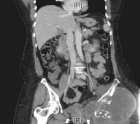

53 year old female with pelvic pain and fevers

History of left hip disarticulation due to a 2005 motor vehicle accident